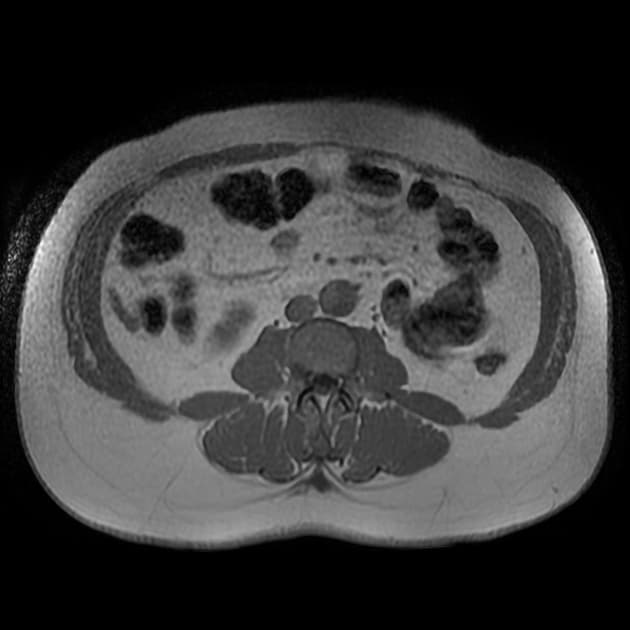

- Thấy vạt bóc tách (flap) trong động mạch chủ (aorta), xuất phát ở đoạn động mạch chủ lên (ascending aorta) ngay phía dưới gốc động mạch chủ (aortic root), xoắn dọc theo toàn bộ động mạch chủ (aorta), tạo thành buồng giả (false lumen) lớn nằm chủ yếu phía sau và chèn ép buồng thật (true lumen), buồng thật có hình bầu dục trên mặt cắt ngang.

- Vạt bóc tách lan xuống đến các động mạch chậu chung (common iliac arteries) ở đoạn trên vùng khảo sát.

- Thấy các cửa sổ thông (fenestration) tại đoạn cung động mạch chủ (aortic arch) gần đoạn gần và ngay trước phân nhánh động mạch chủ (aortic bifurcation).

- Toàn bộ động mạch chủ (aorta) giãn, đường kính lớn nhất tại đoạn động mạch chủ xuống ngực (descending thoracic aorta) đo được 5,1 cm.

- Buồng giả (false lumen) có hiện tượng huyết khối thành mạch (mural thrombus) một phần, không đồng đều, dày nhất ở đoạn động mạch chủ xuống ngực (descending thoracic aorta), làm giảm đường kính lòng mạch khoảng 50%.

- Điểm hẹp nhất của buồng thật (true lumen) nằm ở mức lỗ cơ hoành (diaphragmatic hiatus), đo được 2,9 x 1 cm.

- Thân tạng (coeliac trunk), động mạch mạc treo tràng trên (mesenteric artery) và cả hai động mạch thận (renal arteries) đều xuất phát từ buồng thật (true lumen); các động mạch thận (renal arteries) có vẻ tản rộng do động mạch chủ (aorta) giãn và dịch chuyển.